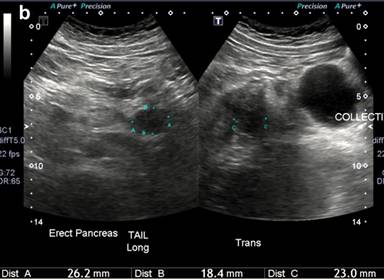

An ultrasound was performed in the emergency which revealed a thickened pancreas and 140 mL of peripancreatic fluid collection at the pancreatic tail. There was fatty infiltration of liver but no gallbladder involvement (Figure 1a). Antibody testing for autoimmune pancreatic insulin insufficiency did not show any abnormalities except a low C-peptide (Table 3). HbA1C was 13.1%. The septic screen performed at initial presentation was normal.

Figure 1. a. Initial ultrasound finding demonstrating edematous pancreas and adjacent fluid collection. b. Follow-up ultrasound demonstrating hypoechoic region consistent with pseudocyst. |

He was commenced on a normal diet day 3 of his admission. Repeat ultrasound showed resolution of pancreatic inflammation and a well-defined hypoechoic region adjacent to the pancreatic tail consistent with a pseduocyst (Figure 1b). He had an additional hypoechoic region in the body of the pancreas suggestive of residual edema.